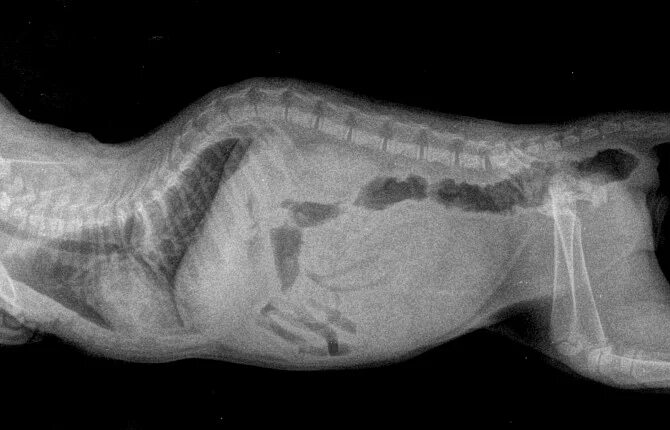

Кошка конвульсии